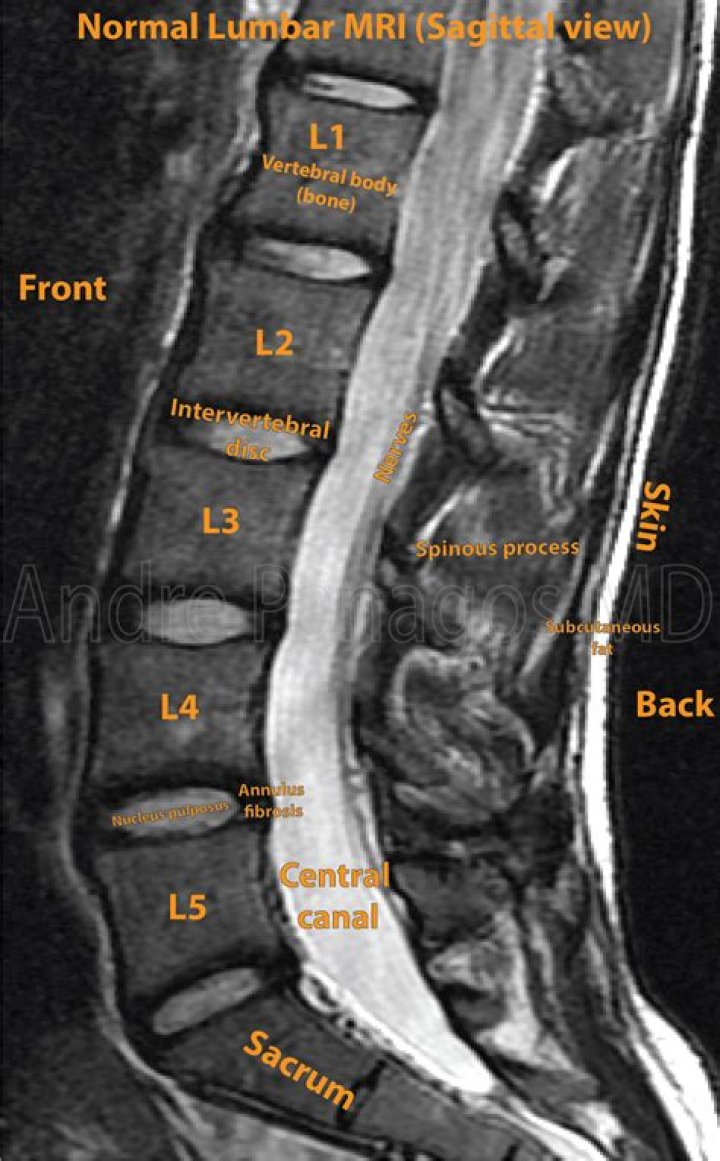

Score: 4.5/5 (32 votes) A lumbar MRI specifically examines the lumbar section of your spine — the region where back problems commonly originate. The lumb...